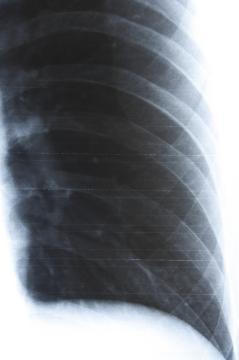

RTG snímek po úrazu

3690XU1 - 16.1.2015 10:35:16 Dobrý den, už celé hodiny hledám lékařskou poradnu online, kde je možné odeslat z otázkou i obrázek. Chtěl bych Vás poprosit o přezkoumání snímku. RTG vzniklo po sedmi dnech úrazu. Smik jsem se na zamrzlé kaluži a měl jsem přitom ruku v kapse. Můj ošetřující lékař mi tvrdí, že na snímku je vše OK, přičemž snímek studoval 4 sekundy. Já se vůbec necítím že by bylo všechno v pořádku.POZNÁMKA: Snímek je na klasickém Filmovém materialu. Tento obrázek jsem získal pomocí silného zábleskového svetla. Píšu to proto, aby jste do úvahy vzali skutečnost, že to není originál. Podezřelé místo jsem vyfotografoval z blízka a zvýšil kontrast aby bylo možné vidět lépe tuto konkrétní část. Srdečně Vám děkuji za odpověď. Jaro.

Dobrý den, bohužel nejsem ortoped ani rentgenolog (a ani nikoho takového v poradně nemáme), ale z mého "laického" pohledu se mi nezdá horní okraj předposledního zobrazeného žebra - vypadá, že je nalomené. Co se týká odborného pohledu, je v podstatě jedno, zda-li jsou žebra naražená nebo zlomená (nalomená), protože léčba je stejná - klidový režim, co nejméně hýbat hrudníkem, tišení bolestí analgetiky. Zlomená žebra se do sádry nedávají, ani nijak nefixují. Všeobecně je známé pravidlo, že naražená žebra bolí více a déle než zlomená.